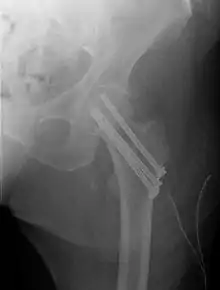

Closed reduction may not be satisfactory and open reduction then becomes necessary.[42] The use of open reduction has been reported as 8-13% among pertrochanteric fractures, and 52% among intertrochanteric fractures.[43] Both intertrochanteric and pertrochanteric fractures may be treated by a dynamic hip screw and plate, or an intramedullary rod.[42]

The fracture typically takes 3–6 months to heal. As it is only common in elderly, removal of the dynamic hip screw is usually not recommended to avoid unnecessary risk of second operation and the increased risk of re-fracture after implant removal. The most common cause for hip fractures in the elderly is osteoporosis; if this is the case, treatment of the osteoporosis can well reduce the risk of further fracture. Only young patients tend to consider having it removed; the implant may function as a stress riser, increasing the risk of a break if another accident occurs.

A lateral incision over the trochanter is made and a cerclage wire is placed around the fracture for reduction. Once reduction has been achieved a guide canal for the nail is made through the proximal cortex and medullary. The nail is inserted through the canal and is fixated proximally and distally with screws. X-rays are obtained to ensure proper reduction and placement of the nail and screws are achieved.[45]